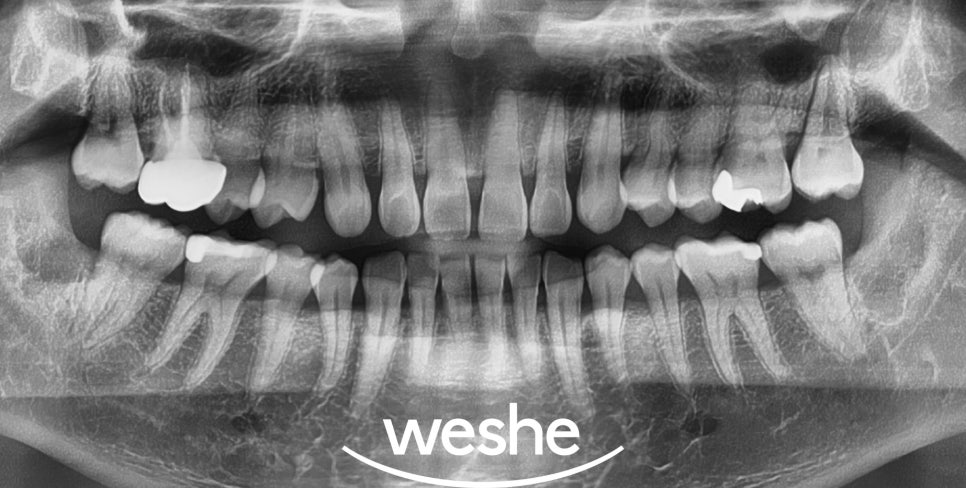

엑스레이 검사를 통해서는

사랑니 주변 염증 상태와

매복 정도를 정확히 파악할 수 있습니다.

네 개의 사랑니(18, 28, 38, 48)에서

관리가 되지 않아 주위 치석과 염증, 충치가

진행되어 발치가 필요하다 판단됩니다.